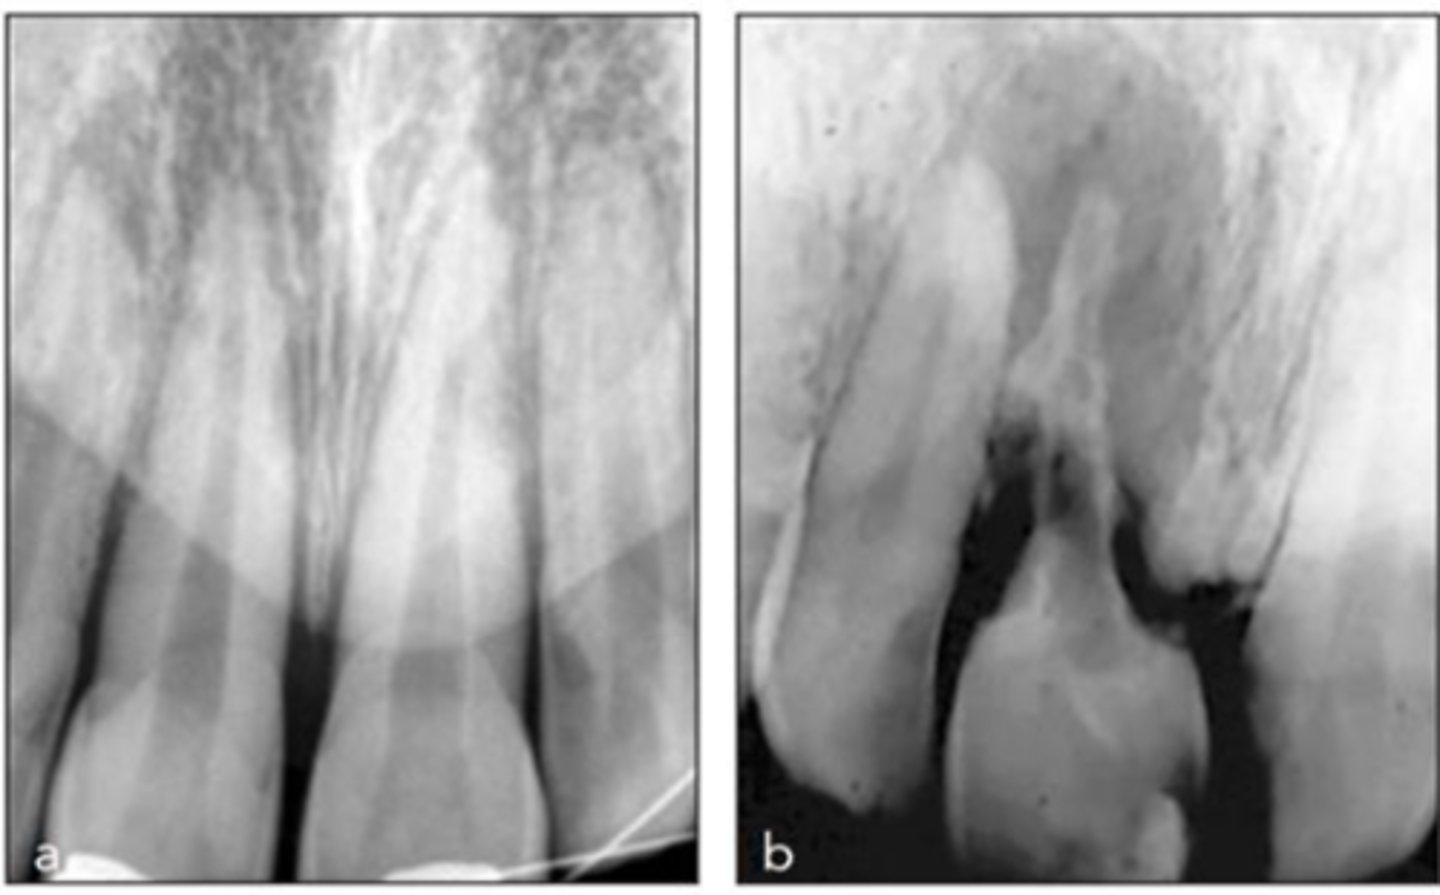

External Replacement Resorption/Ankylosis

Which type of resorption?

- Fusion of cementum or dentin with alveolar bone

Which type of resorption>

- Damage to PDL ⇒ stimulus for surrounding bone to activate osteoclasts and begin resorbing cementum/dentin and replacing it with bone tissue

- Almost always due to trauma (luxation, intrustion, avulsion, replantation)

ID the type of resorption:

CLINICAL

- Characteristic metallic sound on percussion

- May appear infraoccluded in developing dentition

- Lacks physiologic mobility of normal teeth

- May not respond to sensibility testing

RADIOGRAPHIC

- Absence of lamina dura/PDL

- Bone trabeculation occupying previous root surface

- CBCT is often helpful to assess the full extent

Patient presents with these radiographic findings. What is the most likely diagnosis?

- Absence of lamina dura/PDL around lesion.

- Bone trabeculation occupying previous root surface.